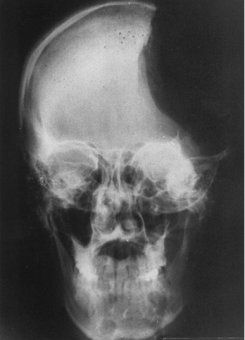

Este libro propone a sus lectores una travesía por la aritmética vista desde los meticulosos ojos de un biólogo, pero sin dejar de lado sus componentes culturales. En los capítulos 1 y 2, al seguir la senda de las habilidades de los animales y los bebés humanos para la aritmética, intentaré convencerlos de que nuestras capacidades matemáticas no carecen de precursores biológicos. En efecto, en el capítulo 3 encontraremos muchas marcas del modo animal de procesamiento de números, activo aun en el comportamiento del humano adulto. En los capítulos 4 y 5, al observar el modo en que los niños aprenden a contar y a calcular, intentaremos comprender cómo puede superarse este sistema inicial aproximado, y qué dificultades supone la adquisición de la matemática avanzada para nuestro cerebro de primates. Esta será una buena oportunidad para investigar los métodos actuales de enseñanza de la matemática y para examinar hasta qué punto se han adaptado naturalmente a nuestra arquitectura mental. En el capítulo 6 también intentaremos esclarecer los rasgos que distinguen a un joven Einstein o a un prodigio del cálculo del resto de nosotros. En los capítulos 7 y 8, por último, nuestro safari seguirá las huellas del número y finalizará en los surcos de la corteza cerebral, donde están localizados los circuitos neuronales que sustentan el cálculo y de donde, ¡ay!, puede desalojarlos una lesión o un accidente vascular, que privan de sentido numérico a sus desdichadas víctimas.